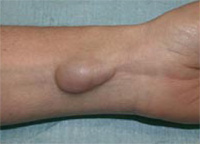

La chondrocalcinose est une arthropathie de précipitation, c’est-à-dire une maladie des articulations qui est souvent confondue avec l’arthrose : des cristaux (de pyrophosphate de calcium) se forment dans le liquide articulaire et se déposent sur les ligaments et les cartilages des articulations et les détruisent. Cette destruction est comparable à celle de la goutte qui est aussi une arthropathie de précipitation due à des cristaux d’acide urique. Les localisations principales de cette affection sont le genou et le poignet. L’affection évolue le plus souvent par crises aiguës: l’articulation qui devient chaude, avec un gonflement visible et des douleurs au mouvement. Ces crises durent de quelques jours à quelques semaines et laissent parfois une articulation déformée.

![]() |

Il arrive aussi que l’évolution soit progressive se manifestant par des douleurs articulaires et des déformations. Cette maladie débute en général après 50 ans , mais le plus souvent après 70 ans, ce qui la rend de plus en plus fréquente en raison de la longévité augmentée. Il existe des formes familiales où le début est plus précoce.

Ce sont les douleur du poignet ou du pouce avec gonflement lors des crises. L’affection peut aussi être découverte par hasard lors d’un traumatisme : pas de douleur, mais à l’examen, limitation des mouvements et de la force. Il n’y a pas de traumatisme dans les antécédents L’age est relativement avancé: 70 ans, en moyenne et l’atteinte est symétrique touchant les deux poignets et parfois les genoux. Parfois, enfin l’affection est révélée par un syndrome du canal carpien qui peut être aigu.

Les signes radiologiques sont souvent très important, même quand les signes cliniques sont modérés ou absents (formes asymptomatiques). Les signes caractéristiques sont: des calcifications, des pincements articulaires localisés ou généralisés, une sclérose osseuse, des géodes osseuses parfois volumineuses. Il n’y a pas d’ostéophytes ni de phénomènes de construction osseuse, ce qui permet de le distinguer de l’arthrose. Les trois localisations les plus typiques sont: la calcification du ligament triangulaire (unissant le radius à l’ulna (cubitus), le pincement isolé de l’articulation scapho-trapèzo-trapèzoïdienne, et l’atteinte des ligaments scapho-lunaire avec dissociation de ces deux os. Plus rarement l’articulation pisi-pyramidale et la médiocarpienne peuvent être atteintes.